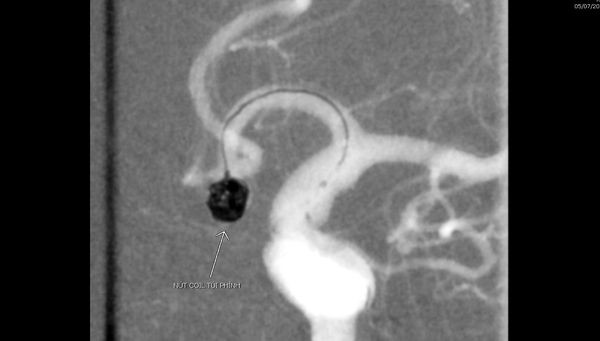

Qua kết quả chụp cắt lớp vi tính, các bác sĩ phát hiện hình ảnh chảy máu khoang dưới nhện do vỡ phình động mạch não thông trước, kích thước túi phình 5x6mm.

Kíp can thiệp do BS.CKII Ngô Quang Chức, Trưởng khoa Chẩn đoán hình ảnh làm kíp trưởng cùng các bác sĩ, kỹ thuật viên trong khoa tiến hành luồn vi ống thông từ động mạch đùi lên đoạn mạch não bị tổn thương, tiếp cận túi phình động mạch não thông trước và thực hiện nút bít túi phình bằng vòng xoắn kim loại (Coil) dưới hệ thống chụp mạch số hóa xóa nền 2 bình diện (DSA).

Kết quả chụp mạch kiểm tra thấy, túi phình bị vỡ đã được bít hoàn toàn, tuần hoàn động mạch não hồi phục trở lại.

Túi phình động mạch não thông trước được coil bít lại hoàn toàn |

Túi phình động mạch não thông trước được coil bít lại hoàn toàn